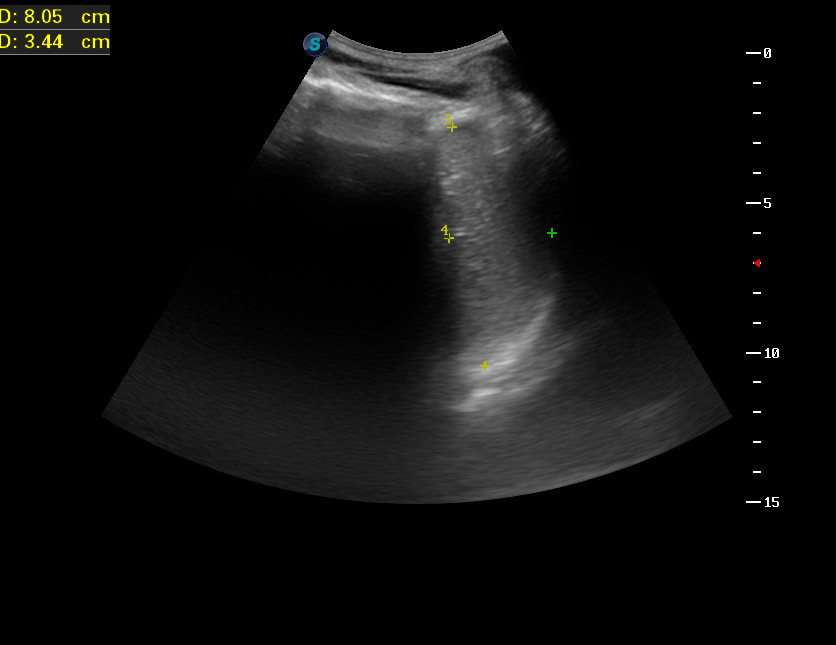

Свежее исследование

20171024_090513_10.jpg

Какие будут мнения?